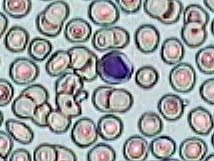

Imágenes tomadas de las preparaciones de los alumnos de 3º ESO sobre un frotis sanguíneo

214x161 píxeles